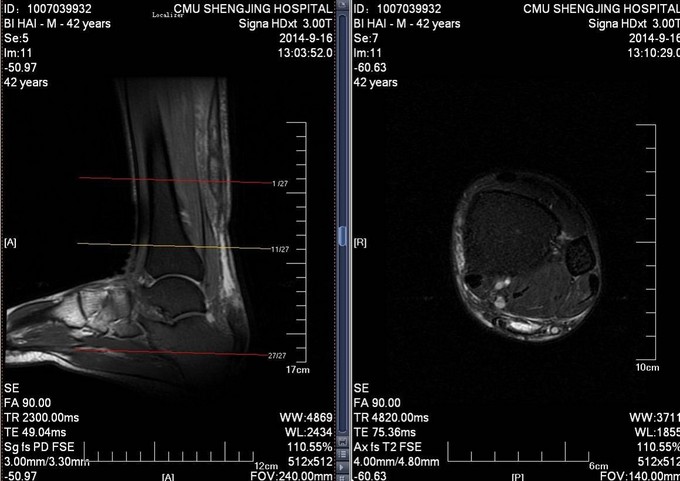

患者于2014年7月28日打排球时不慎摔伤,自觉左足跟部一过性剧烈疼痛,意识清醒。自觉足跟部及小腿后侧远端疼痛、行走时左足无力。于2014年9月10日就诊于当地医院,行相关查体后提示:左脚跟腱断裂。患者为进一步治疗门诊以“左跟腱断裂”为诊断收入病房

患者生命体征平稳,跟腱后方凹陷。局部可触及缺损,Thompson征阳性。

诊断:左陈旧性跟腱断裂 入院完善检查后,行左跟腱翻转修补术,术后踝关节跖屈石膏固定。